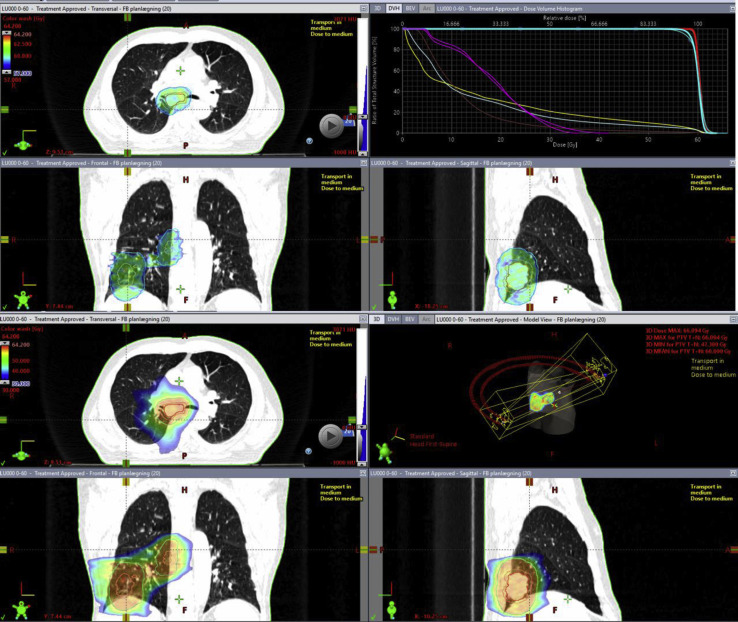

The patient was referred for chemoradiotherapy regimen of 60 Gy in 30 fractions (Fig. 1 ) with a total of three cycles of platinum-doublet chemotherapy.

Figure 1.

Radiotherapy treatment plan. The upper panels revealing the dose color wash in the range of 95% to 107% (i.e., 57–64.2 Gy), along with the dose volume histogram. Gross tumor volume is in red, clinical target volume in orange, planned target volume in cyan, lungs in light blue, heart in brown, esophagus in yellow, and spinal cord and spinal cord planning risk volume in magenta. The lower panels reveal dose color wash in the range of 50% to 107% (i.e., 30–64.2 Gy), along with the plan geometry with two half arcs for volumetric-modulated arc therapy treatment.